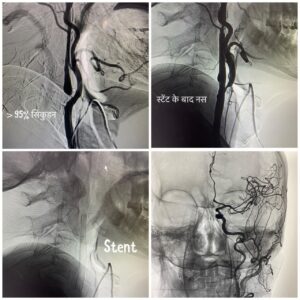

ऋषिकेश। एम्स की कार्यकारी निदेशक एवं सीईओ प्रोफेसर (डॉ.) मीनू सिंह के निर्देशन में संस्थान के इंटरवेंशन रेडियोलॉजी विभाग में उच्च तकनीकी वाले न्यूरो इंटरवेंशन जैसे कैरोटिड स्टेंटिंग (खून की नस में सिकुड़न ) ए.वी.एम व ए.वी.एफ( खून की नसों का गुच्छा) , स्ट्रोक (लकवा) एन्यूरिजम (खून की नसों का गुब्बारा व नसों का फटना) समेत कई अन्य तरह की बीमारियों का बिना किसी चीरफाड़ के इलाज उपलब्ध है। बताया गया है कि यह उपचार एम्स अस्पताल में मरीजों को बीते आठ महीने से आयुष्मान भारत योजना के तहत निशुल्क दिया जा रहा है।

संस्थान में यह कार्य दिल्ली एम्स से प्रशिक्षित एवं वर्तमान में एम्स ऋषिकेश के इंटरवेंशन रेडियोलॉजी विभाग (भूतल बी- ब्लॉक) में कार्यरत सहायक आचार्य डॉ. बी.डी. चारण (डी.एम. न्यूरोइंटरवेंशन) द्वारा मरीजों में इस तरह की बीमारियों के उपचार को अंजाम दिया जा रहा है।

विषय विशेषज्ञ डॉ. बी.डी. चारण ने बताया कि विभाग की डीएसए लैब (पांचवीं मंजिल ) में उपचार की यह प्रक्रिया एनेस्थीसिया विभाग के सहयोग से संपन्न की जाती है, जिसमें अन्य विभागों जैसे जेरियाट्रिक मेडिसिन, ईएनटी, नेत्र विभाग, न्यूरोसाइंस व मेडिसिन आदि का भी योगदान रहता है।

डॉ. चारण के मुताबिक इस विधि के तहत जांघ की खून की नस में 2 एमएम का पाइप डालकर ब्रेन तक पहुंच बनाई जाती है, उसके बाद बीमारी का बिना चीरफाड़ किए इलाज किया जाता है। उन्होंने बताया कि चूंकि इस उपचार में चीरफाड़ नहीं किया जाता है, लिहाजा मरीज को अस्पताल अथवा आईसीयू में निहायत कम समय तक ही रुकना पड़ता है और मरीज की जल्दी छुट्टी कर दी जाती है।